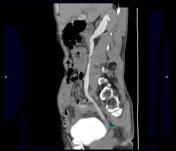

问题 男,53岁,无痛性血尿2个月余,CT扫描如图示,下列说法正确的是 ( )

选项 A、考虑为输尿管移行细胞癌 B、考虑为输尿管内血块 C、软组织肿块边缘毛糙不平 D、其上方的输尿管扩张 E、右侧输尿管下段可见沿输尿管走行的软组织肿块影

答案 ACDE